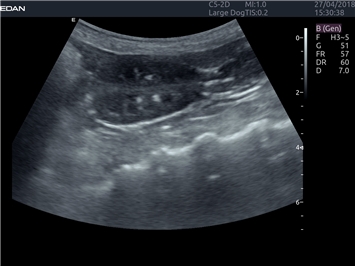

EDAN Acclarix LX4 VET представляет собой профессиональную ультразвуковую систему, специально разработанную для ветеринарных исследований. Сочетание стабильности, высокой производительности и эффективности делает эту систему идеальным выбором для современной ветеринарной практики.

B-режим, Двухмерное сканирование:

Да